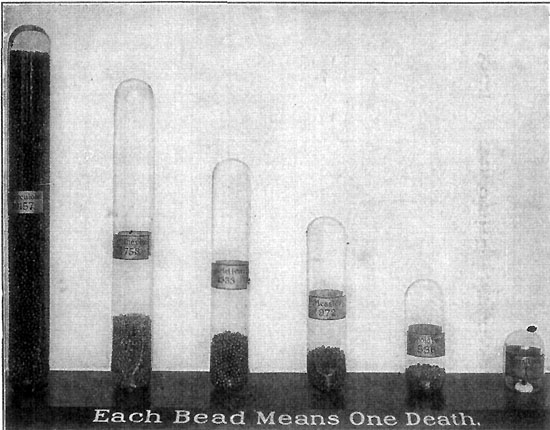

156 A Year of Consumption on Manhattan Island

157 Consumption in Chicago

161 A Comparative Death-Rate from Contagious Diseases